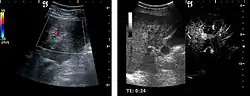

HCC appearance on 2D ultrasound is that of a solid tumor, with imprecise delineation, with heterogeneous structure, uni- or multilocular (encephaloid form). An "infiltrative" type is also described which is difficult to discriminate from liver nodular reconstruction in cirrhosis. Typically HCC invades liver vessels, primarily the portal veins but also the hepatic veins . Doppler examination detects a high speed arterial flow and low impedance index (correlated with described changes in tumor angiogenesis). The spatial distribution of the vessels is irregular, disordered. CEUS examination shows hyperenhancement of the lesion during the arterial phase. During the portal venous phase there is a specific "wash out" of ultrasound contrast agent (UCA) and the tumor appears hypoechoic during the late phase. Poorly differentiated tumors may have a stronger wash out leading to an isoechoic appearance to the liver parenchyma during portal venous phase. This appearance was found in approx. 30% of cases. The described changes have diagnostic value in liver nodules larger than 2 cm.

Spectral Doppler characteristics of early HCC overlap those of the dysplastic nodule, as they are represented by the presence of portal venous signal type or arterial type with normal RI (well differentiated HCC) or increased RI (moderately or poorly differentiated HCC). The CFM exploration identifies a chaotic vessels pattern.